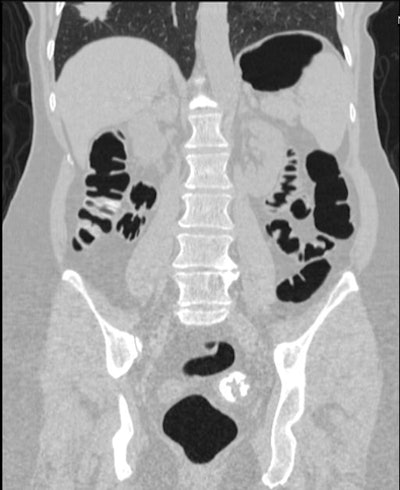

![]() |

| Coronal image shows unsuspected cancer (partially imaged spiculated mass) involving the right lung. All images courtesy of Dr. Perry Pickhardt. |